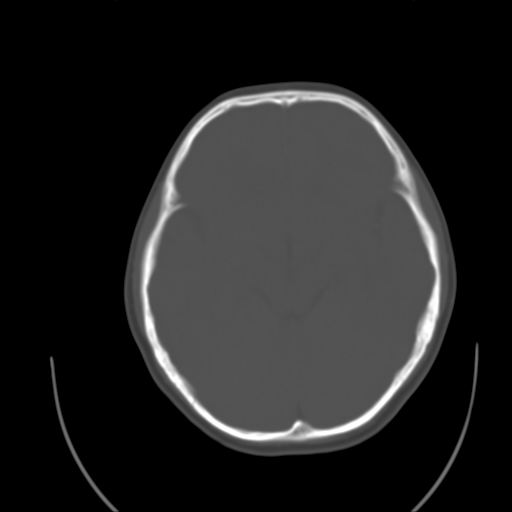

标题: PED1738:男 9岁左枕部包块。 [打印本页]

标题: PED1738:男 9岁左枕部包块。

猛一下想不起这个叫什么了,惭愧,请老师指导~~

左枕部头皮下血肿,有外伤史吗?

枕骨结节

左枕部皮下软组织密度增厚影---考虑-----左枕部头皮下血肿

考虑皮样囊肿可能性大

皮样囊肿可能性大.

皮样囊肿?皮下脂肪瘤?

软组织囊肿性病变可能性大

皮样囊肿?

考虑皮样囊肿。

考虑皮样囊肿可能性大。

皮样囊肿可能性大。